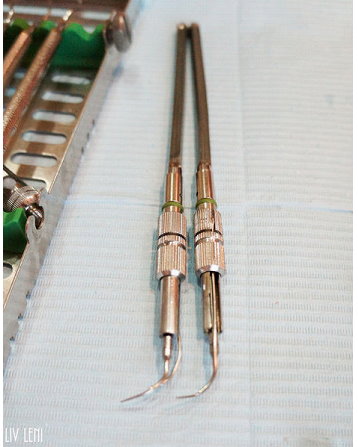

醫師會先拿一根 牙周探測器,插入牙齦溝測量深度,

健康時,牙齦溝的深度大約1~3釐米,

大於3釐米就表示已形成囊袋,越深代表牙周破壞越嚴重。

光用手指觸碰無法得到正確讀數,要利用兩支鈍端的器械,

通常是口鏡及牙周探測器的柄,才能測得牙齒鬆動的程度。

這是清除牙菌斑顯示劑的工具。

每次做完牙菌斑顯影,

診所都會貼心的再幫我們清除乾淨唷(不需要自己動手刷的要命XD)

這個步驟是醫師拿牙周探測器,

測量經過刮除治療與正確刷牙後,牙周囊袋有無改善。